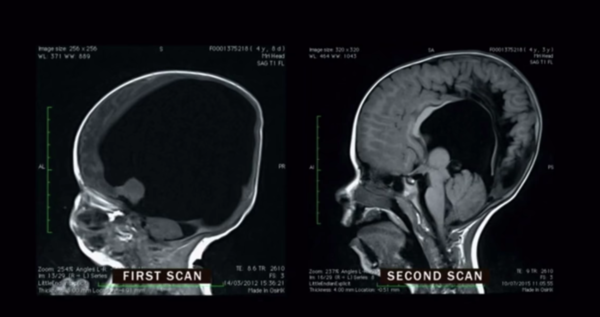

Uzun bir süre sonra mucize gerçekleşti. Noah’ın beyni hızla gelişmeye başladı. Yaşıtlarına oranla beyin gelişimi yavaş olsa da tahmin edilenlere göre çok hızlı bir gelişmeydi bu. Artık o da diğer çocukların yaptıklarını yapabilecekti. Dört yaşına geldiğinde ise yaşıtlarıyla arasında hiçbir fark kalmadı.